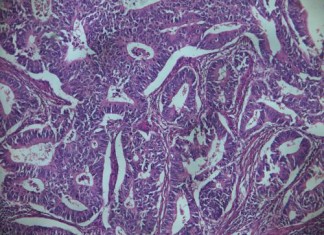

El colesterol ayuda en el crecimiento y propagación del cáncer de...

Un subproducto de funciones para el colesterol como la hormona estrógeno ayuda a impulsar el crecimiento y la propagación de los tipos más comunes...